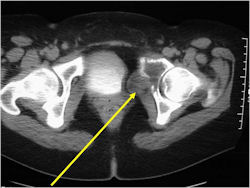

- Pelvis

Radiographic Presentation

- Permeative or moth eaten bone destruction

- Ill defined and malignant appearing

- Bony changes are often subtle

- Soft Tissue Mass in 90% of of cases

- Pelvic Ewing sarcoma have a worse prognosis than other areas